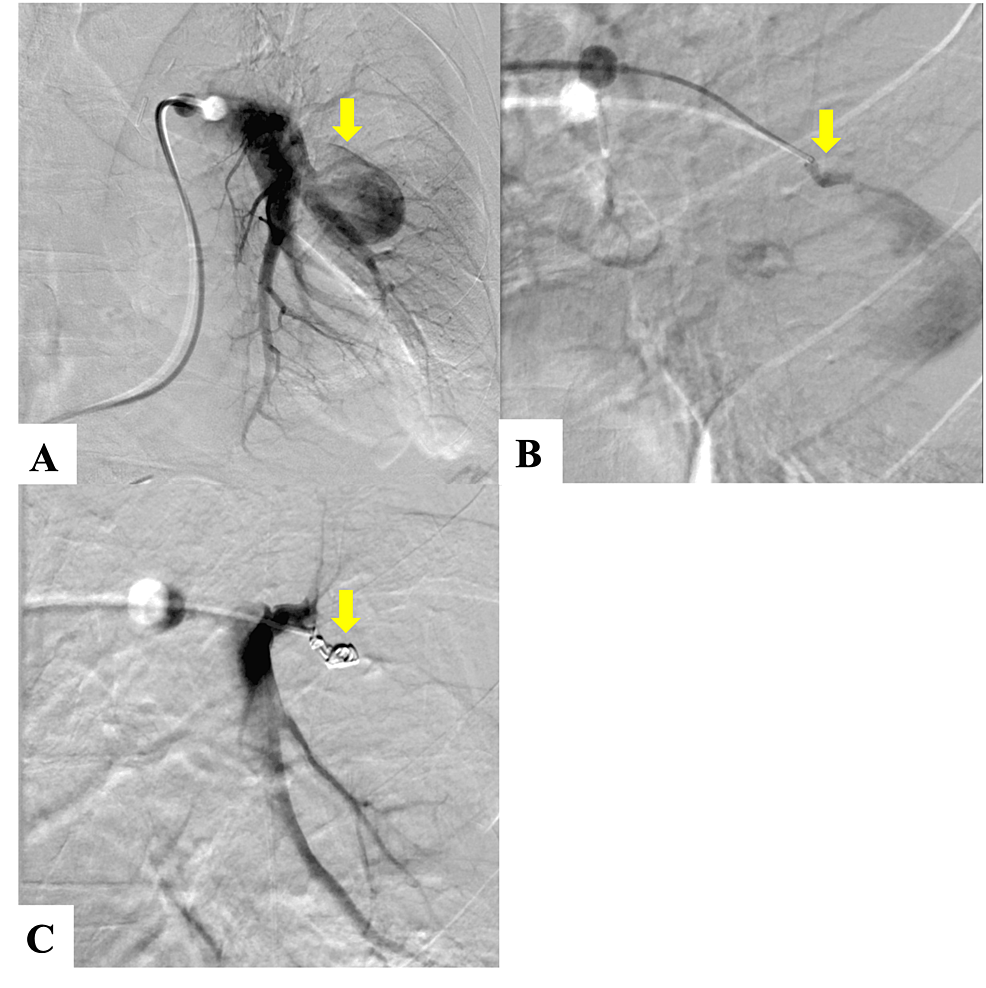

Coil Embolization of Pulmonary Sequestration in Two Infants A Safe

Coil Embolization of Pulmonary Sequestration in Two Infants A Safe Coil Embolization Lung Coil embolization of both the nidus and feeding artery was associated with a higher occlusion rate (94.3%) compared with distal. Coil embolization can be a lifesaving treatment for large vessel perforations. Pavm treatment is challenging even in the most experienced hands. Embolization of pulmonary avms greatly reduce these risks. Pulmonary arteriovenous malformations (pavms) are most often associated with hereditary hemorrhagic. Coil Embolization Lung.